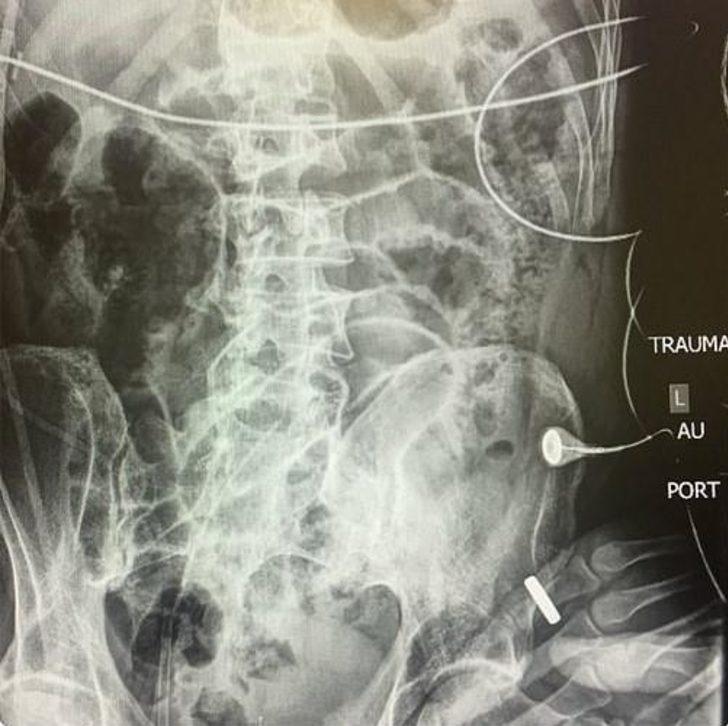

Bu paylaşımın ardından doktorlar sosyal medya üzerinden bir akım başlattı ve herkes silahlı yaralanma sonucu hastaneye getirilen hastalarının fotoğraflarını paylaştı.